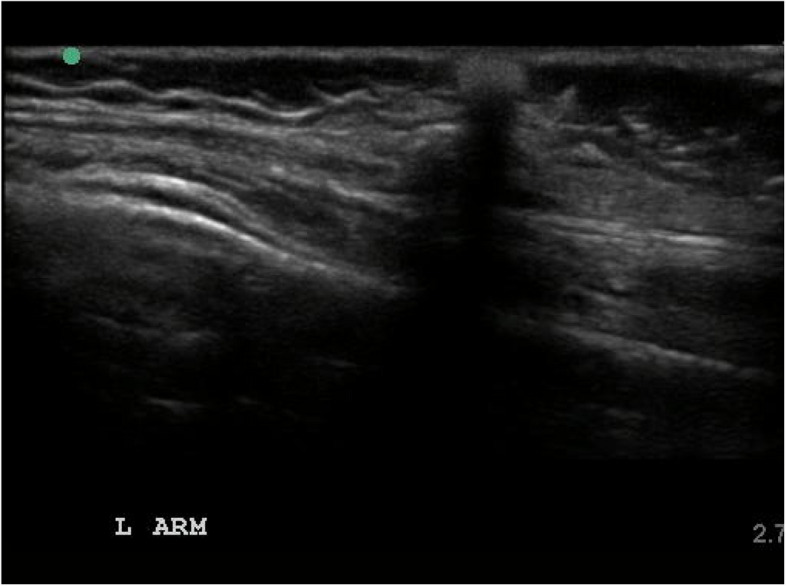

Calcinosis is a severe manifestation of juvenile and adult idiopathic inflammatory myopathies, which can lead to pain, limited range of motion, disfigurement, and infection. It is more common in juvenile idiopathic inflammatory myopathies, especially in juvenile dermatomyositis (JDM). Calcinosis can be visible on cutaneous surfaces, although can also present in muscles and internal organs, making a thorough assessment difficult without imaging modalities. In this narrative review, we discuss different imaging modalities used in evaluating JDM-associated calcinosis including X-ray, computed tomography (CT), magnetic resonance imaging (MRI), and ultrasound (US).